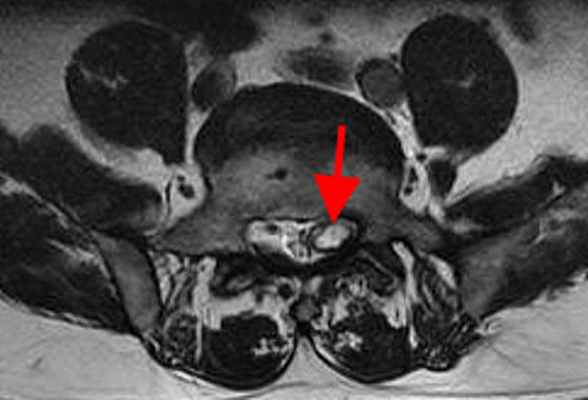

б) Визуализация экстрадуральной арахноидальной кисте крестца:

• Равномерное правильной формы расширение спинномозгового канала крестца:

о Раздвигает, однако не нарушает целостность костных стенок крестца

о Отсутствует расширение или ремоделирование крестцовых отверстий

• Характерно наличие вдавление в области задней стенки крестца

• Отсутствие контрастного усиления стенки кисты

(Слева) На этой схеме пояснично-крестцового отдела позвоночника показана экстрадуральная киста, расположенная в спинномозговом канале ниже окончания дурального мешка на уровне S2. Обратите внимание на ремоделирование костных стенок спинномозгового канала на уровне кисты.

(Справа) Т1-ВИ, сагиттальная проекция: в спинномозговом канале крестца определяется небольшая экстрадуральная киста, интенсивность сигнала которой соответствует жидкости. Такая локализация типична для скрытого крестцового менингоцеле, которое в настоящее время носит название экстрадуральной арахноидальной кисты. В полости кисты не определяется ни солидного, ни жирового компонентов. (Слева) На сагиттальном Т2-ВИ в каудальной части спинномозгового канала визуализируется небольшая экстрадуральная арахноидальная киста крестца. Конус спинного мозга оканчивается на нормальном уровне. Обратите внимание на то, что интенсивность сигнала от кисты несколько выше, чем от СМЖ в дуральном мешке, что отражает повышенное содержание в полости кисты белка.

(Справа) Аксиальное Т1-ВИ крестца на уровне арахноидальной кисты подтверждает некоторое ремоделирование костных стенок каудальной части спинномозгового канала, вызванное объемным воздействием кисты.